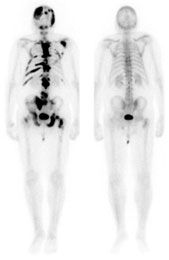

Before treatment (left) and after (right)

In a phase II randomized trial, cabozantinib (XL184), an investigational oral tyrosine kinase inhibitor, demonstrated antitumor activity in multiple types of advanced solid tumors. Prostate cancer, ovarian cancer, and hepatocellular carcinoma had the highest disease control rate, which combines partial response and stable disease. In an unexpected additional outcome, cabozantinib reduced or eliminated bone metastases in patients with breast and prostate cancers, as well as melanoma.

Bone scans also revealed that bone metastases decreased in 59 of 68 patients who had bone lesions. These results were confirmed through an independent review conducted by radiologists. The researchers had expected the tumor response based on preclinical studies of cabozantinib; however, they were surprised at the bone lesion activity, according to co-author Nicholas J. Vogelzang, MD, chair and medical director, developmental therapeutics committee and US Oncology research medical oncologist, Comprehensive Cancer Centers of Nevada in Las Vegas. The bone metastases improvement largely occurred in patients with CRPC, with complete or partial bone scan resolution in 86% of CRPC patients.